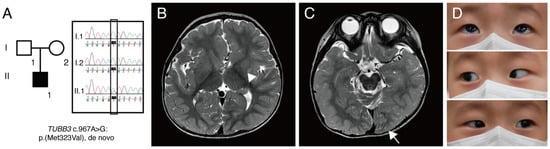

Figure 1. (A) A pedigree of patient reported in this study. Square, male; round, female; black coloring, affected individual. Targeted next-generation sequencing showed TUBB3 c.967A>G:p.(M323V) variant. Sanger sequencing confirmed that this variant is a de novo mutation. (B) Brain magnetic resonance imaging showing cortical dysplasia. T2-weighted images without contrast revealed an asymmetric caudate nucleus (arrowhead) and globular shape of both basal ganglia and thalamus. (C) Axial T2-weighted image showing an asymmetric configuration of an occipital lobe (arrow) and abnormal cerebellar vermian foldings. (D) Pictures of an extraocular motility examination showing a full range of motion.

Subsequently, brain magnetic resonance imaging (MRI) was performed, and it revealed an asymmetric configuration and size of caudate nuclei and asymmetric configurations of lateral ventricles, occipital lobes, and corpus callosum, which are consistent with cortical dysplasia (Figure 1B,C). Repeated examination of extraocular motility had shown full duction and version until the age of 23 months (Figure 1D), and 2-Hz left-beating jerk nystagmus and intermittent head nodding were observed. A non-sedated hand-held ERG test (RETeval, LKC Technologies, Gaithersburg, MD, USA) using skin electrodes was performed for the diagnosis of retinal dysfunctions associated with nystagmus. The scotopic response was normal, but the result was inconclusive due to poor patient cooperation (Figure 2). Neurological examinations showed no gross or fine motor delays. He could sit, walk, and even run without support, but mild intellectual disability and mild language delay were noted.